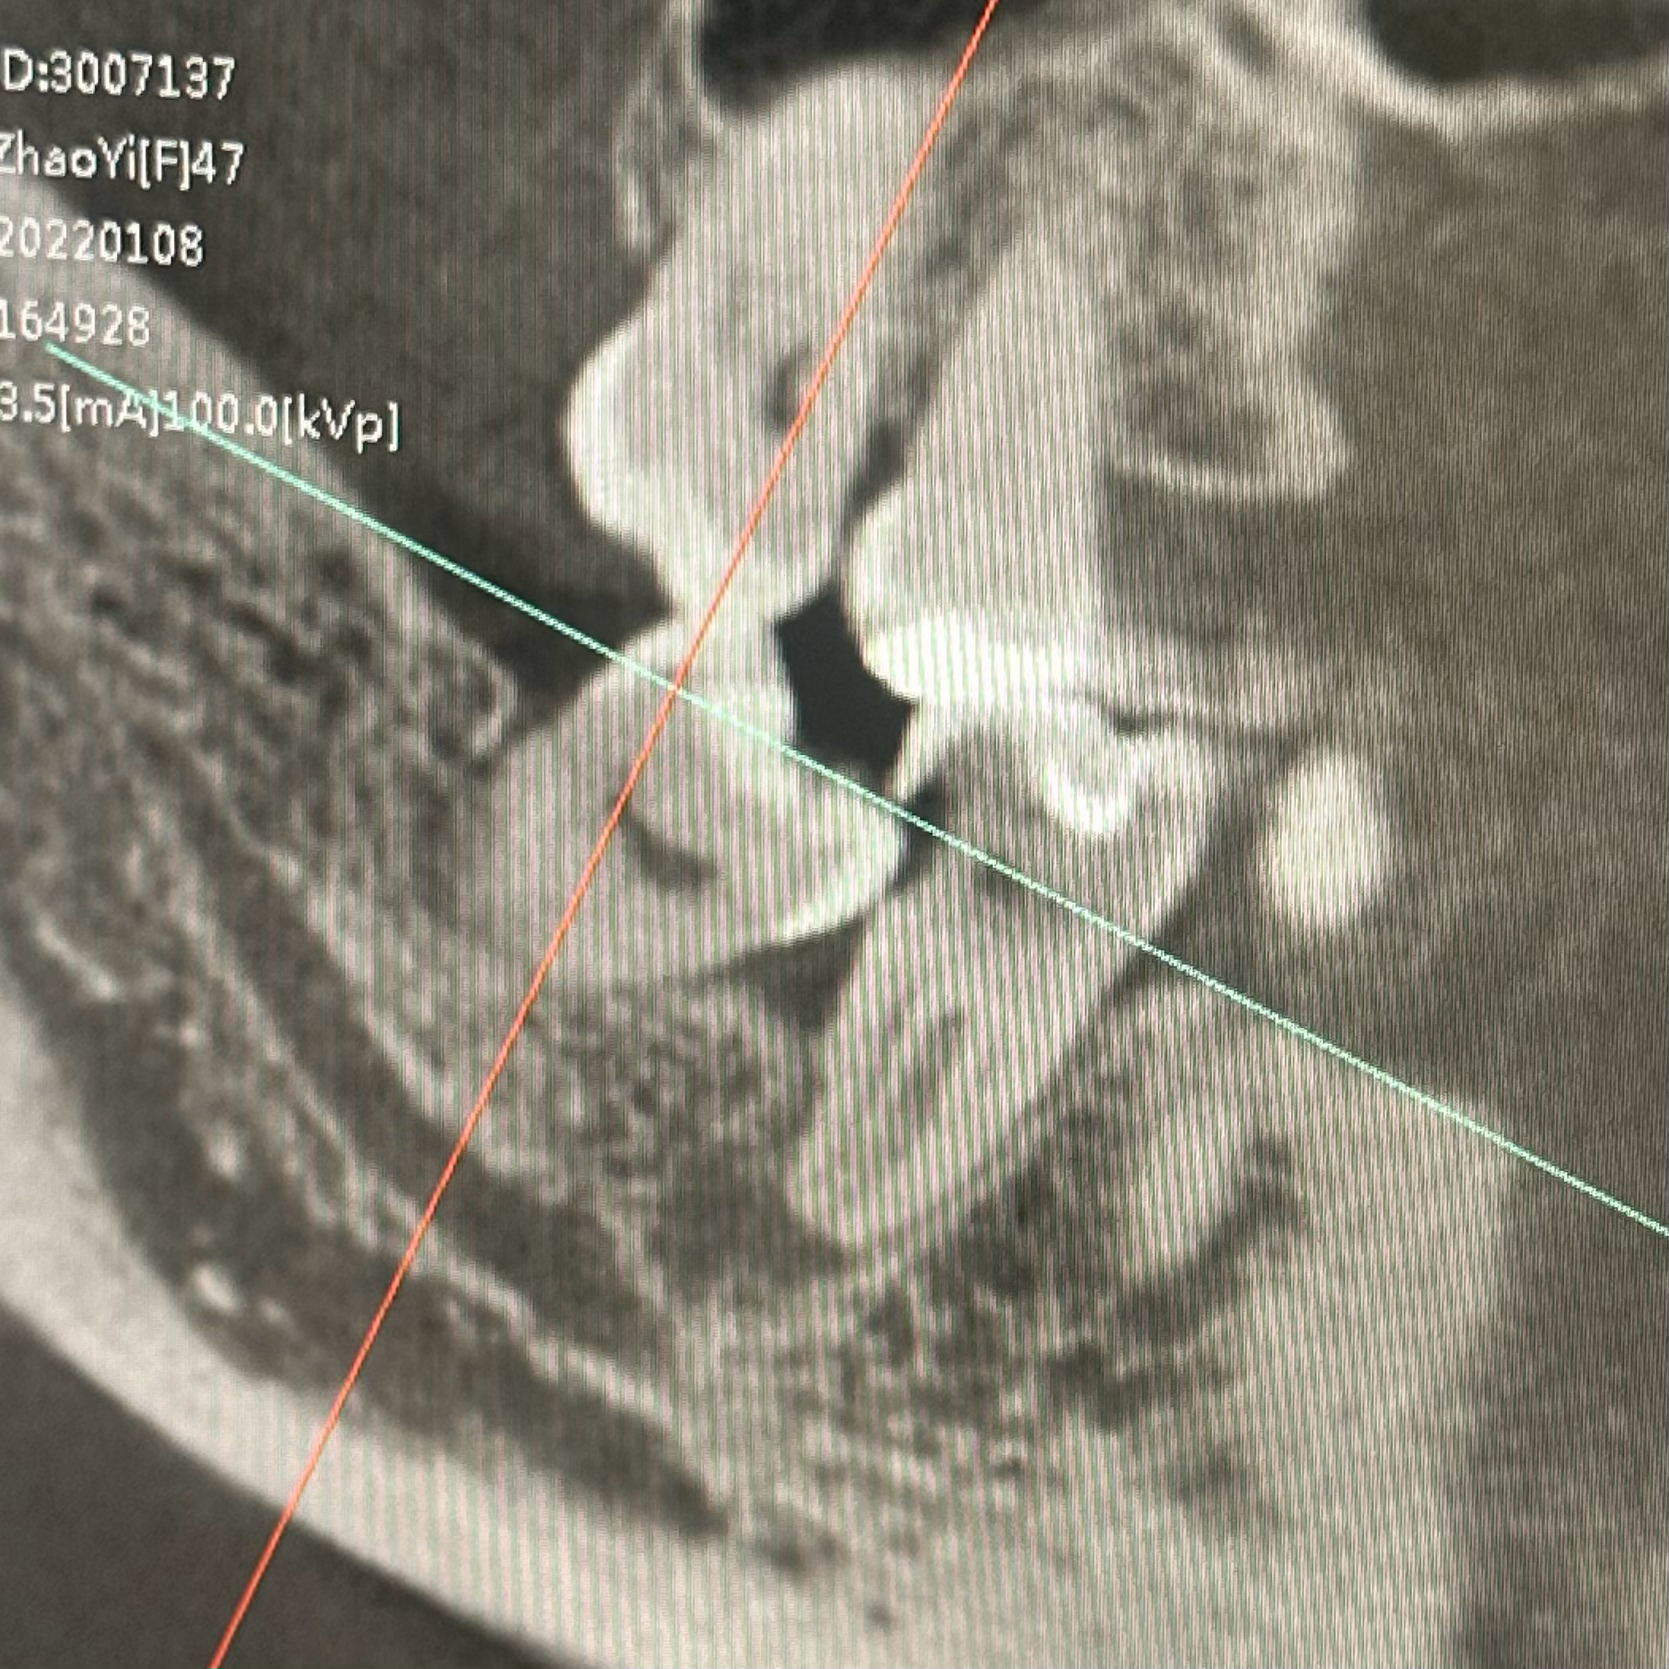

图一:

被挤破并累及到神经,

情况变复杂,

需要处理神经之后做烤瓷牙。

一个月都处理不完,

还得去三四次。

图四:

还有一颗横着长的智齿,

也可能挤到旁边牙的压根,

要不要手术取出,

还没跟林医生商量,

处理完被挤出洞的那颗牙之后再说吧。